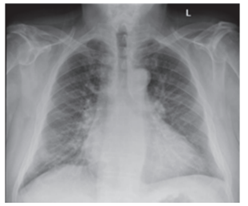

Homem 67 anos de idade, portador de hipertensão arterial e diabetes melito tipo II, apresentando tosse seca e dispneia progressiva nos últimos três meses. Atualmente, tem dispneia para subir pequenos aclives. Relata ortopneia e edema em membros inferiores. Ao exame físico, apresentou PA de 150x90 mmHg, FC de 95 bpm, TEC < 2 segundos. Estertores finos basais bilateralmente e discreto edema maleolar. Eletrocardiograma: ritmo sinusal e sobrecarga ventricular esquerda. Ecocardiograma: fração de ejeção do ventrículo esquerdo 30%, hipocinesia difusa. Radiografia de tórax apresentada a seguir:

Enunciado 3685503-1

Em relação ao caso descrito e à imagem apresentada, qual deve ser a conduta terapêutica neste momento?